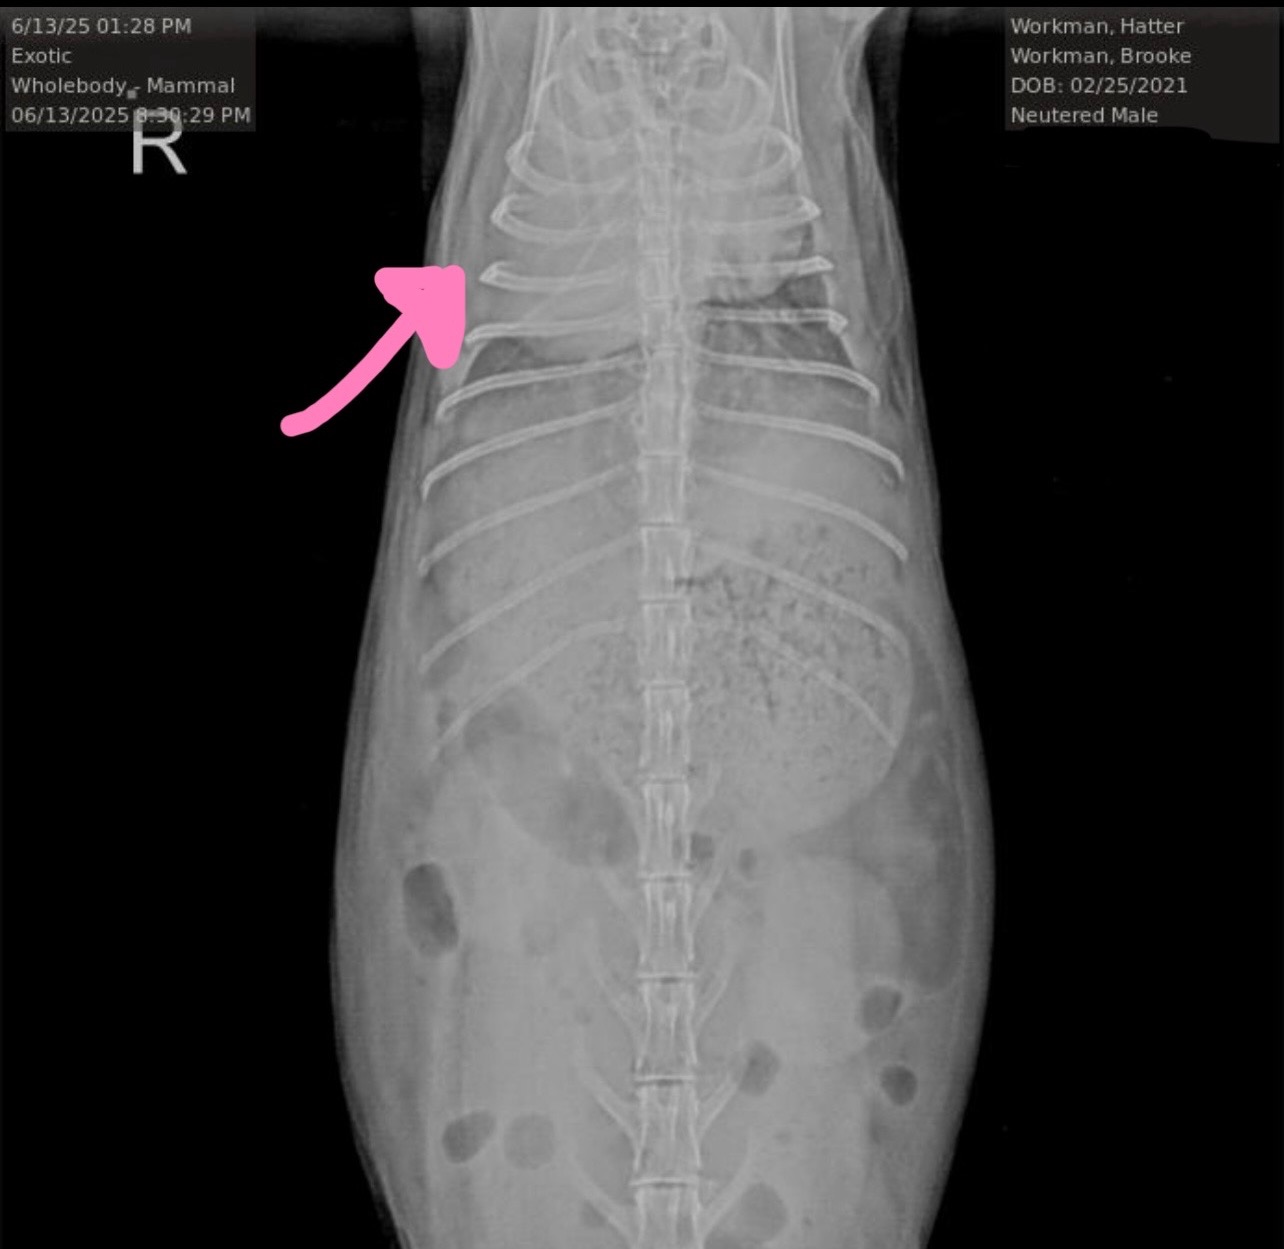

He recently had an X-ray, which shows a mass in his chest, one that was not there 10 months ago. He’s already showing signs of it starting to put pressure on his lungs and windpipe, causing discomfort and even GI issues.

The X-ray results were devastating, but they also gave us a chance to act before it becomes immediately life-threatening.